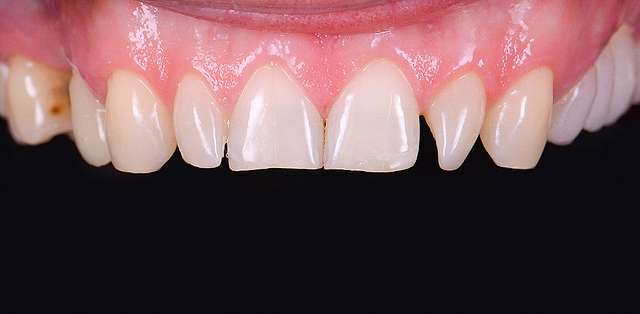

A mock-up is the visual side of a treatment plan. Consider the treatment plan as something scriptic, that contains price estimates and procedures, some hard to understand. Consider the treatment plan as the text , whereas the mock-up is the drawing meant to explain it. Traditionally the mock-up was used to test prosthetic design of a future restoration. In present times the mock-up is used at the beginning of most rehabilitations to express visually the esthetic impact of the proposed treatment plan. The entire process is non invasive and reversible. The mock-up is transferred on top of the existing teeth, whenever possible , and a series of optical ilusions is used in order to simulate the future smile. Generally it is communicated to the patient via pictures or videos, that will serve as the draft for communication between patient and the team treating him.

The mock-up just like a treatment plan can simulate a diverse array of procedures that vary on cases basis. In this case, we have dental implants and tissue grafts in posterior areas, on both sides, and ceramic veneers and crown lengthening in anterior side to balance the smile. As a fine detail , you can see how the dentist uses a black marker to simulate the area of the tooth which will be reduced. The mock-up, once accepted becomes a cental pillar in an interdisciplinary treatment. It will be used to determine how the gums will be remodelled , where the implants should be placed, and how the teeth need to be prepped for the future restorations.